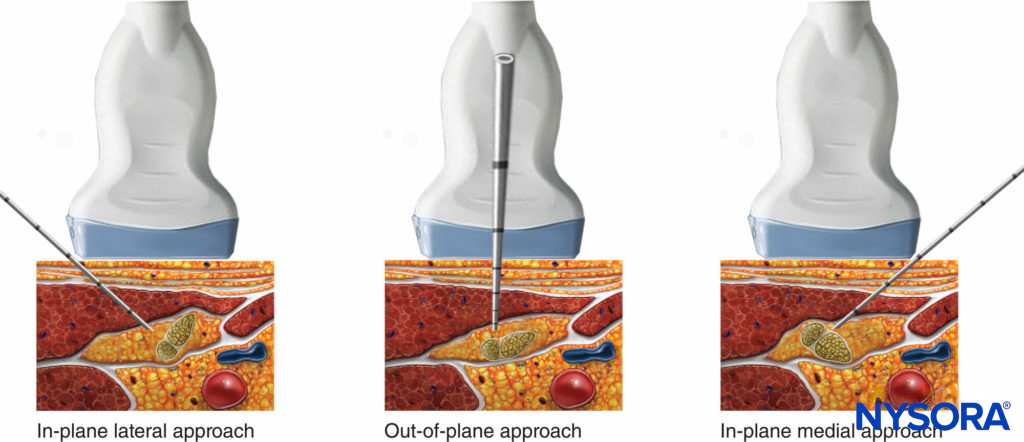

For the posterior approach, the needle is inserted in plane from lateral to medial (Figure 9) or out of plane (Figure 10). If nerve stimulation is used (0.5 mA, 0.1 msec), the contact of the needle tip with either branch of the nerve usually is associated with a motor response of the calf or foot. Once the needle tip is placed within the common sciatic nerve sheath, 1–2 mL of local anesthetic is injected to confirm the proper injection site. Such injection should result in a distribution of local anesthetic within the sheath, and separation of the TN and CPN within Vloka’s sheath (Figure 11).

- In the posterior approach to the popliteal nerve block, either an in-plane (lateral or medial) or out-of-plane technique can be used (Figures 9 through 12). While the in-plane lateral approach is commonly used, the advantage of the out-of-plane approach is that the needle path is through the skin and adipose tissue rather than the muscles and thus, less painful.

FIGURE 12. In-plane (lateral or medial) or out-of-plane approach are shown – the operator should be able to pick and choose any of these needle orientations, depending on the configuration of tibial and common peroneal branches at the site of injection.